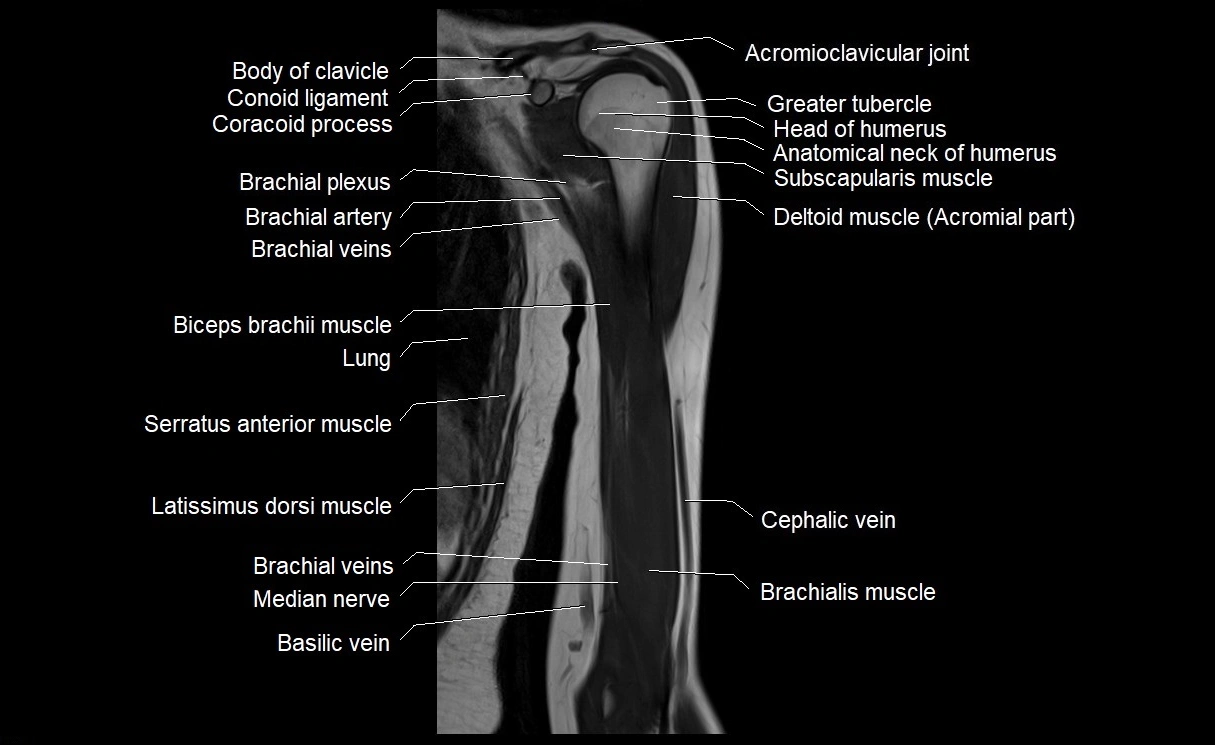

- Biceps brachii muscle

- Brachial artery

- Brachialis muscle

- Cephalic vein

- Basilic vein

- Coracobrachialis muscle